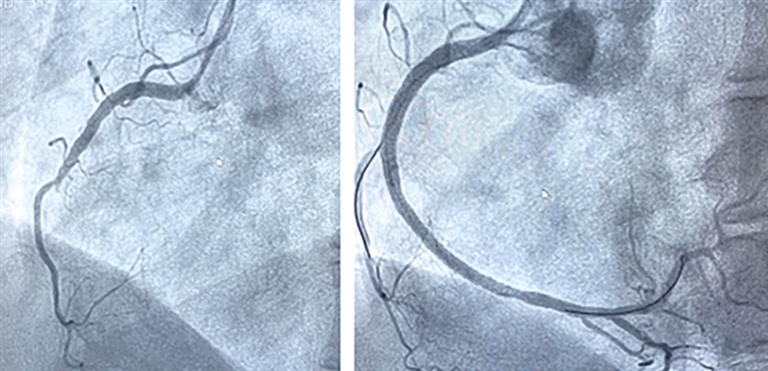

左图术前右冠中段完全闭塞,右图术后右冠完全开通。

情况紧急,胸痛中心迅速响应,与家属沟通并签署知情同意书,同步办理住院手续,全程开通绿色通道,用最快的速度把吕女士送入导管室接受急诊PCI治疗(经皮冠状动脉介入治疗)。在王宁夫主任医师指导下,徐鹏和钱宇峰副主任医师为她进行介入治疗,术中发现她的右侧冠状动脉近段完全闭塞,通过球囊扩张并植入支架,成功开通了堵塞的血管,恢复了心肌供血。